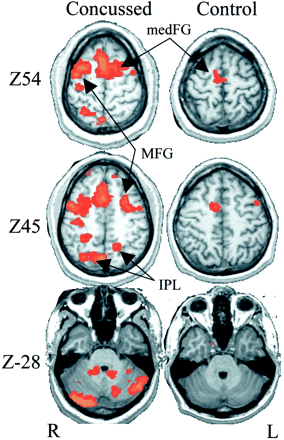

Although within-subject increases in BOLD signal intensity were observed for most subjects tested on at least a subset of the tasks, increases were considerably greater for concussed players, as shown for two representative subjects in Figure 3. In the control subject, increases in activity were relatively small and, in the case shown, restricted to the SMA and a small region of the left dorsal premotor cortex. In striking contrast, the concussed individual demonstrated large, extensive increases in regions associated with executive functioning, such as working memory and motor planning. These areas included the SMA, bilateral premotor cortex, superior and inferior parietal regions, and bilateral aspects of the cerebellum.

Representative individual Z-score differences between baseline and either a postconcussion session (concussed, left) or postseason baseline sessions (control, right). Colored areas show regions of activity that significantly increased from the baseline value of the bimanual sequencing task. Although both concussed and control subjects demonstrate some increases, those of the concussed player are considerably larger. Activity is significantly increased in the medial frontal gyrus (medFG), middle frontal gyrus (MFG), inferior parietal lobe (IPL), and bilateral cerebellum.